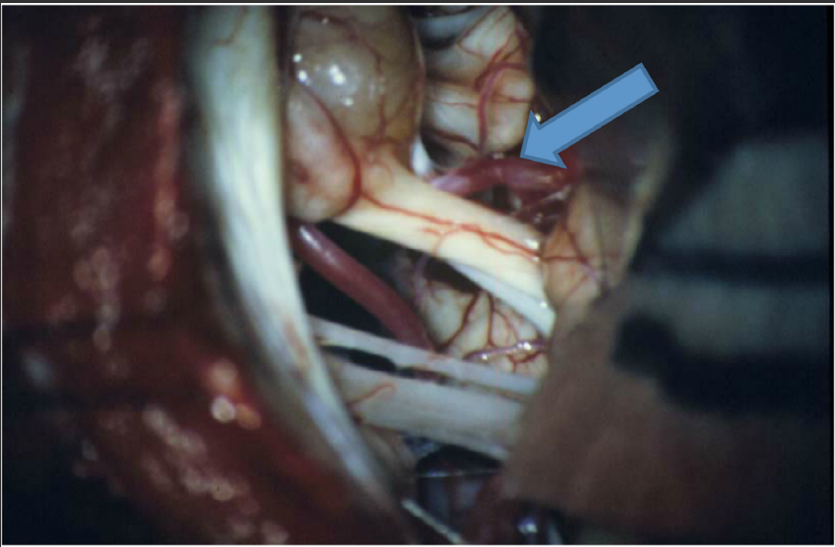

What artery (identified by the arrow in Figure 1) is encountered during a retrosigmoid approach for a vestibular schwannoma?

B. Anterior inferior cerebellar artery.